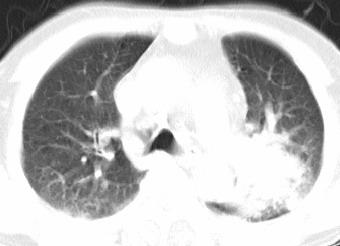

以下是引用xianxianzhongyi在2008-4-20 14:44:00的发言:[br]本人愚见:次病例短短两月的时间,呈现如此大面积实变,病变增长过于迅速,此其一。其二,病变在动脉早期既有明显强化。其三,左上叶后段及下叶背段多叶受累。其四,肺门及纵隔内未见明显肿大的淋巴结。估计层面较厚段支气管显示不清。 诊断:炎性实变可能性大。

以下是引用光影相伴在2008-4-20 14:39:00的发言:[br]支持:1)左侧中央型肺癌伴左肺上叶阻塞性肺炎。、[br] 2)双侧少量胸腔积液。